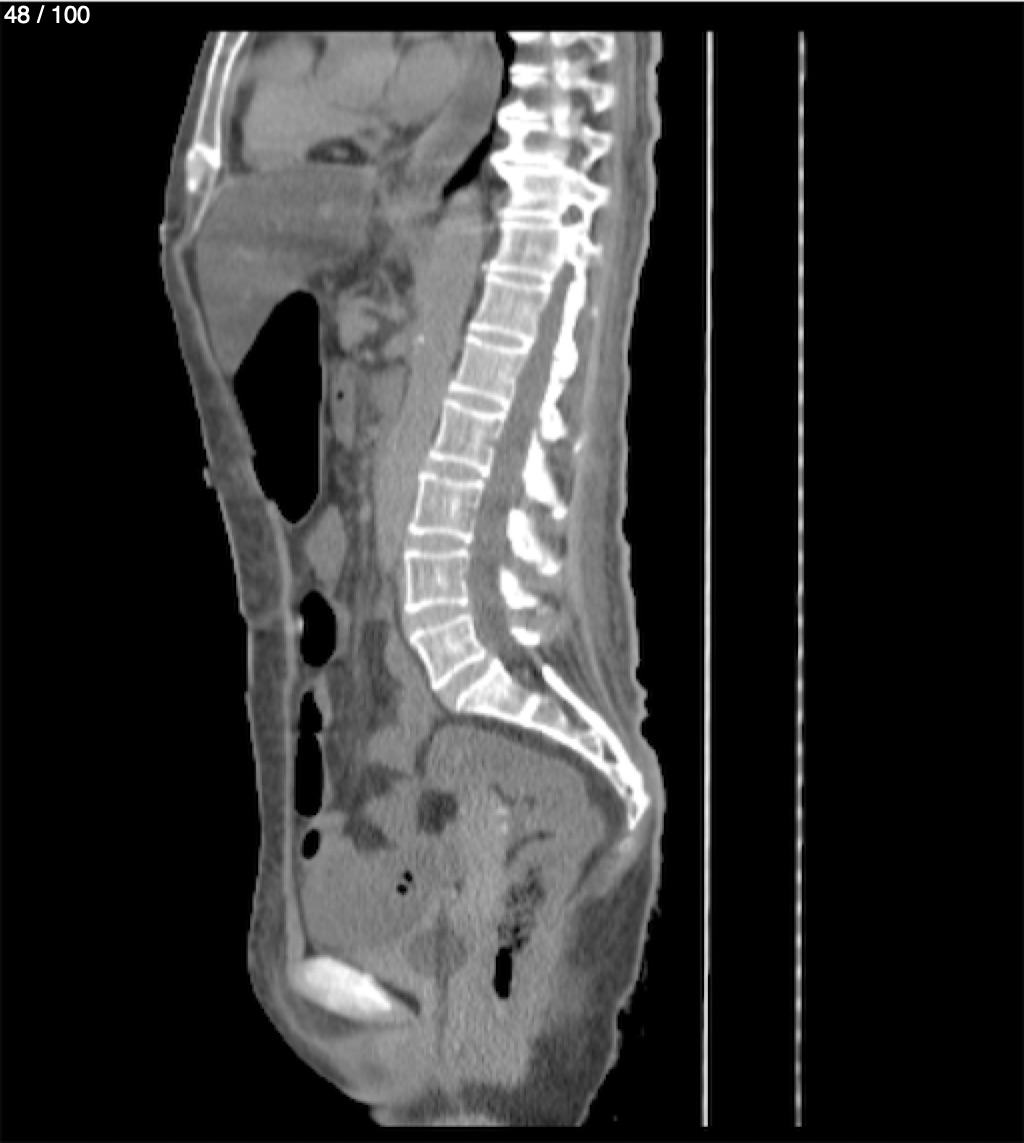

Hilda Geronimo Mendez 60A - T.C Abdomen Simple